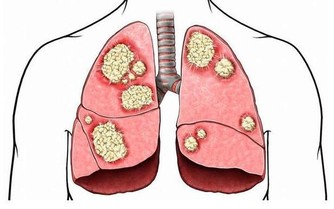

腳這個地方變黑,你就要小心了!!可能是癌症前兆…一定要注意了!!千萬不要忽視。。。。。。 小編就帶你一下你不知道的那些腳部信號的暗示以及一些需要注意的養生常識。看看以下哪些情況是你有過的吧。 1、足部的黑點 我們總是把皮膚癌和日曬聯繫起來,所以我們通常不會檢查腳上的黑點。然而,作為皮膚癌中最危險的黑素瘤,就可能發展到不經常接觸陽光的部位。黑素瘤甚至可能出現在腳指甲下面,看起來像是個黑點兒。 2、腳趾有「黑痣」 我們經常會在身體各個部位看到大小不同,甚至凹凸不平的黑點,這些黑點我們稱之為「黑痣」。腳趾上更是容易看到這些黑痣。那麼黑痣和癌症又有哪些聯繫呢?黑痣本身是天然無公害的,但是黑痣一旦惡化,演變成皮膚癌變將會危及我們的生命安全,即我們經常所說的癌變。 腳趾上的黑痣由於其特殊的位置就很有可能演變成為黑色素瘤。

惡性黑色素瘤是皮膚癌的一種,雖然在中國還不是很常見,但是在歐美地區卻是常見的惡性腫瘤之一。在我國不常見並不意味著黑痣對人體是無害的,近幾年來皮膚癌在我國的發病率也逐漸升高,所以我們還是需要了解其產生的原因,事先做好防護措施,防患於未然。 為什麼說腳趾上的黑痣更容易演變成癌症因子呢?因為黑痣在正常情況下癌變的機率是比較小的,但是如果經常遇到摩擦、擠壓,將會增大其癌變的可能性。我們的腳趾常年處於摩擦和擠壓的狀態下,所以更加容易造成癌變。 黑痣本身就是我們身體與生俱來的良性腫瘤。後天由於生活環境的影響以及自身各個器官的病變,導致了其進一步惡化為黑色素瘤。 還有一部分認為,黑痣只有在暴曬的情況下才會演變成黑色素瘤,但是我們正常情況下是不會暴曬到腳趾部位的。所以我們會容易忽略掉腳趾上的「癌症病毒」。但是,作為皮膚癌中最危險的黑色素瘤,是非常容易發展到不經常接觸陽光的部位。黑素瘤甚至可能出現在腳趾甲下面,看起來就像是一個普通的黑點。 所以如果腳趾部位出現黑痣的話,請大家要做好保護措施,經常觀察黑痣是否有異常變化,如果出現異常請儘快就醫。 3、勺子狀的腳指甲 有時對指甲的傷害或是長期接觸石油基質溶劑可能造成凹陷的像勺子一樣的腳趾形狀。同時,缺鐵也可能會形成這種特殊形狀。